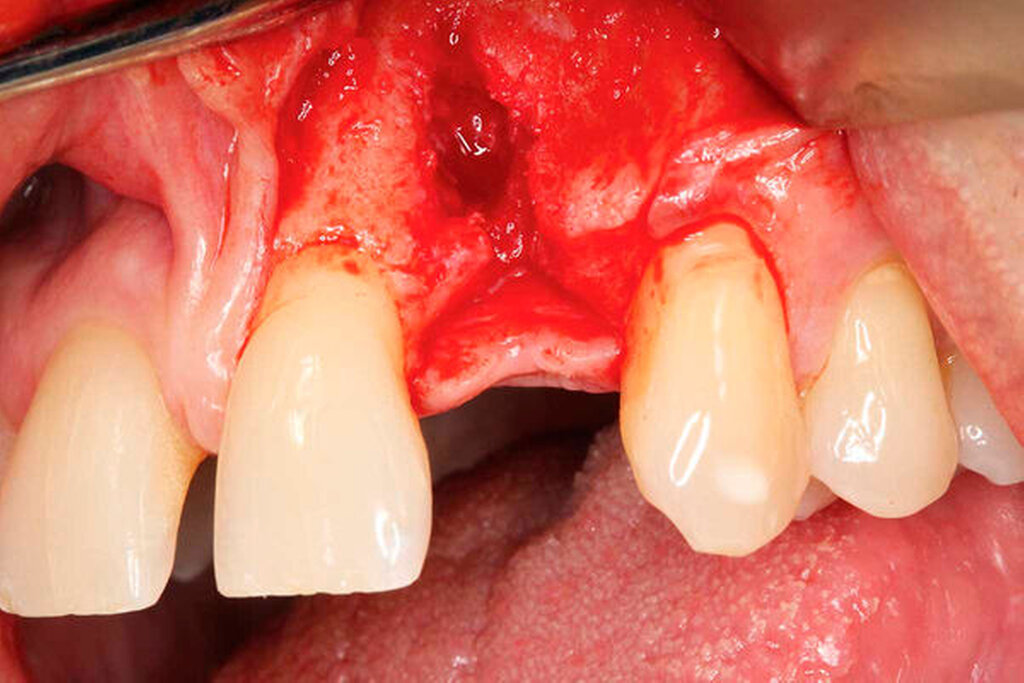

Nach Lappenbildung und Darstellung des Kieferkamms erfolgte die Aufbereitung des Implantatlagers gemäß Protokoll des Implantatherstellers. Anschließend wurde ein Implantat (ASTRA TECH Implant SystemTM EV, Dentsply Sirona, York, USA) inseriert (Abbildungen 3a bis 3c).

Die zuvor gewonnene und aufbereitete Dentinscheibe wurde mit Osteosyntheseschrauben (microscrews, Stoma, Emmingen-Liptingen, Deutschland) lateral des Defekts fixiert und das aufbereitete Dentinpartikulat in den Hohlraum zwischen Zahnscheibe und Implantat eingebracht (Abbildung 3d). Der Wundverschluss erfolgte spannungsfrei mit nichtresorbierbarem Nahtmaterial (Supramid 5/0, Serag-Wiessner, Naila, Deutschland). Postoperativ wurde ein DVT als Röntgenkontrolle angefertigt. Dieses zeigt das Implantat regio 22 in der Sagittalebene. Deutlich erkennbar ist die fixierte Zahnscheibe (Abbildung 4a).